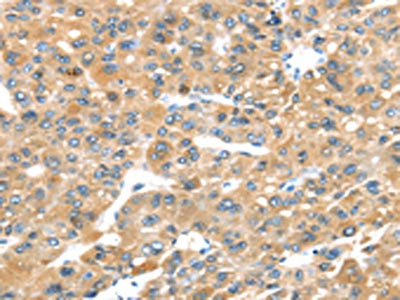

The image on the left is immunohistochemistry of paraffin-embedded Human liver cancer tissue using CSB-PA576176(P2RY2 Antibody) at dilution 1/30, on the right is treated with synthetic peptide. (Original magnification: ×200)